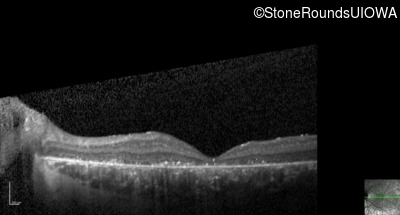

Optical Coherence Tomography - Right - 5/200

Exemplar / OCT Stack